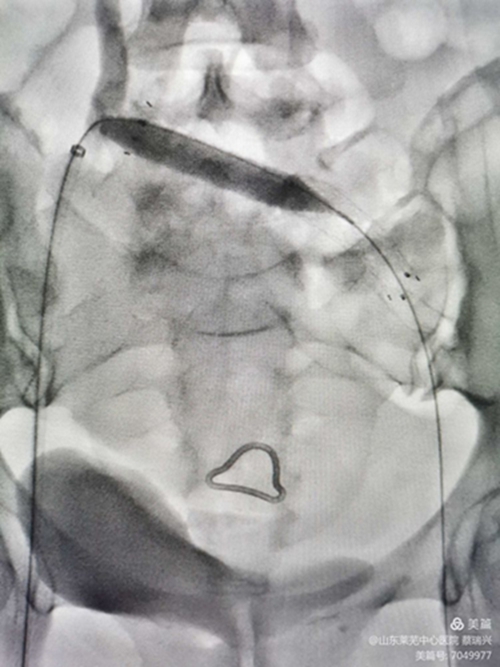

女性,55歲,左下肢腫脹2天入院,疼痛,無明顯功能障礙。左下肢I(xiàn)I度水腫,脹力高。彩超示,左下肢股淺靜脈、股總靜脈、髂外靜脈血流不暢,見有血栓,呈低回聲。髂總靜脈觀察不清。肺動(dòng)脈CTA示無栓塞。取右股靜脈入路,造影證實(shí)左髂總靜脈閉塞,開通后,左下肢深靜脈造影示左下肢股淺靜脈、股總靜脈、髂外靜脈均有充盈缺損,留置溶栓導(dǎo)管6天。今天給予左髂總靜脈支架成形術(shù)。如圖,溶栓導(dǎo)管造影證實(shí),左髂總?cè)杂兄囟泉M窄,血流不暢,易再閉。

與右髂總匯合處,重度狹窄。

取出濾器,預(yù)行左髂總靜脈成形術(shù),但又閉塞,導(dǎo)管不能通過。

釋放支架,行后擴(kuò)張,球囊有“腰征",且很窄,考慮閉塞段像"噗"一樣。

噗征